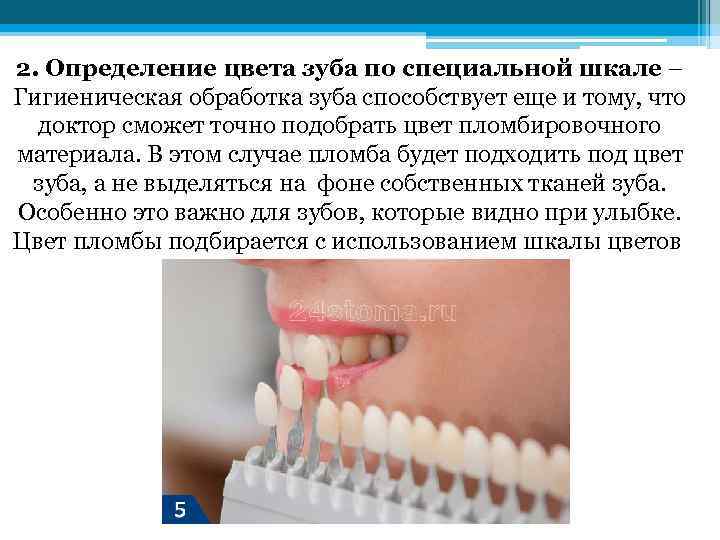

2. Определение цвета зуба по специальной шкале – Гигиеническая обработка зуба способствует еще и тому, что доктор сможет точно подобрать цвет пломбировочного материала. В этом случае пломба будет подходить под цвет зуба, а не выделяться на фоне собственных тканей зуба. Особенно это важно для зубов, которые видно при улыбке. Цвет пломбы подбирается с использованием шкалы цветов

2. Определение цвета зуба по специальной шкале – Гигиеническая обработка зуба способствует еще и тому, что доктор сможет точно подобрать цвет пломбировочного материала. В этом случае пломба будет подходить под цвет зуба, а не выделяться на фоне собственных тканей зуба. Особенно это важно для зубов, которые видно при улыбке. Цвет пломбы подбирается с использованием шкалы цветов